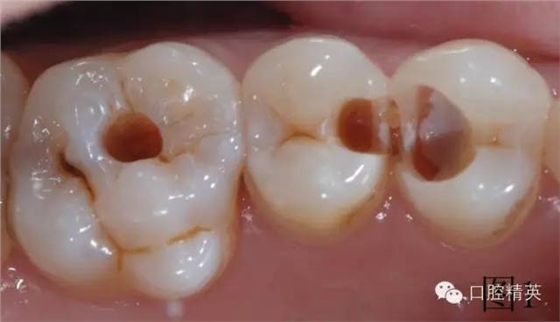

患者自覺左上第一磨牙有洞,檢查發(fā)現(xiàn)小面積充填物脫落,左上第一前磨牙大面積齲壞,離牙神經(jīng)很近但未漏神經(jīng),光固化經(jīng)氧化鈣墊底,去腐過程中發(fā)現(xiàn)左上第二前磨牙近中隱蔽齲壞,腐質(zhì)全部去凈,制備窩洞,如圖1。